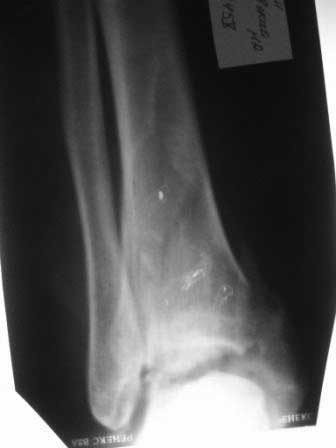

Уважаемые коллеги, хотелось бы услышать как прооперировать этот злополучный перелом

(интерисует погружной синтез)?

Извините за качество снимков! Если сможите разобрать, то: 1)Какой доступ

предпочтительней? 2)Каким образом устранить тенденцию к подвывиху кпереди (не будет ли

проблемой оскольчатость переднего края)? Заранее спасибо! С уважением А.Мелёшкин!